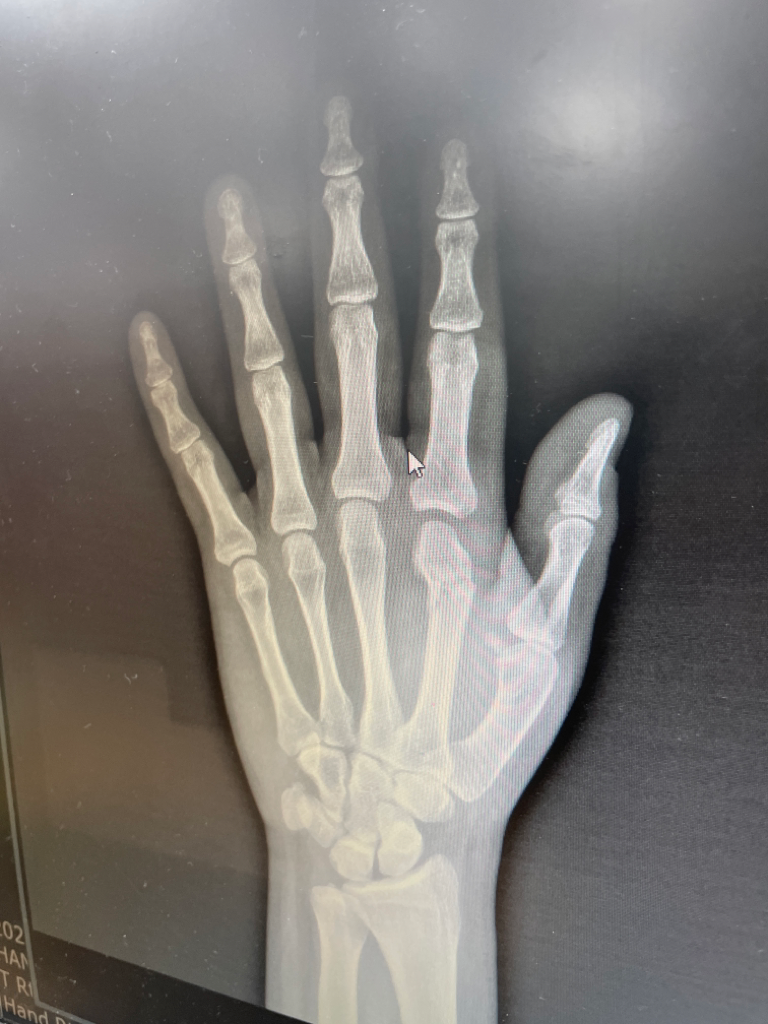

중수부 골절 심한 편인가요 지금?

검지 2번째 중수부 골절 판단을 받았습니다 골절이 심한 편인가요 제가 내일 당장 출근을 해야하는데 큰일났습니다.. 걱정이 이만 저만이 아닙니다 낫는데 오래걸릴까요 또 수술은 꼭 필요한가요? 비수술로 낫고 싶은데

엑스레이만으로는 판단이 어렵습니다. 중수부 골절 소견이 보이며 수술 여부는 정형외과 주치의와 상의 후 결정하는 것이 좋겠습니다. 일반적으로 골절이 치유되는데는 적어도 4-10주 정도 소요되며 이는 부위마다 다를 수 있습니다.

각도가 많이 변형되어 있어서 그대로 골유합이 이뤄질경우 손을 쥐고 펴는데 문제가 있을수도 있습니다.

뼈가 크게 어긋나 있지는 않아보입니다.

현재 중수골 원위부 골절로 인해 관절부위의 변형이 온 상태로 깁스로의 치료에는 한계가 있을 것 같으며, 추후 기능장애의 발생가능성이 높습니다.

그렇기 때문에 수술적 치료를 시행하시는 것이 좋겠습니다.